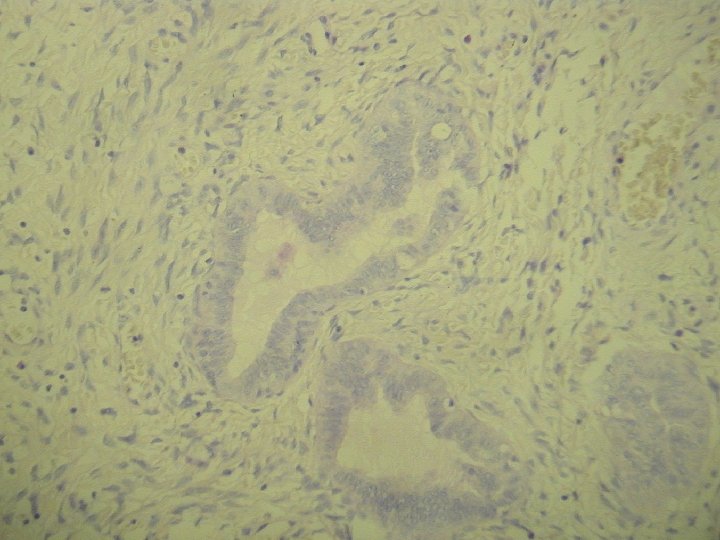

prolaps tuby asociovaný s exuberantnou angiomyofibroblastickou strómou

Ø hladkosvalové vlákna a lymfoplazmocytárny infiltrát Ø bohatá vaskularizácia v retiformnej stróme, miestami aj myxoidnej Ø Imuno: silná desmin pozit. Ø CD 34, S-100, alfa aktin, CK, calponin negat. Ø prezentovaná reaktívna stromálna proliferácia publikovaná v dvoch „case reportoch“